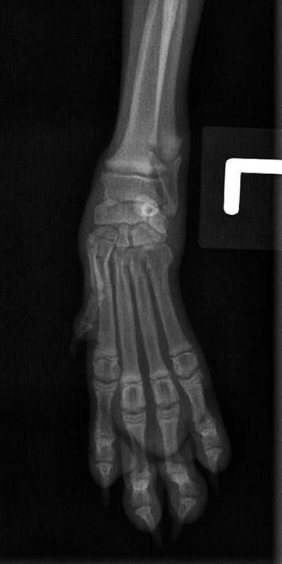

what radiograph view of the carpal joint is shown?

lateral view

what radiograph view of hte carpal joint is shown?

lateral view with carpal joint flexed at 90 degrees

what position do we put the animal in for a dorso-palmar view of the carpal joint and digits?

sternal recumbency with affected forelegs extended cranially and head elevated away

what radiograph view of the carpal joint and digits is shown?

dorso-palmar view

what digits are taped if we are doing a splayed lateral view of the digits?

digits 2 to 5

what radiographic view of the digits is shown?

splayed lateral view of the digits

what is circled in orange?

sesamoid bone in the tendon of m. abductor pollicis longus

what is the yellow line?

radiocarpal joint

what is the berry red line?

intercarpal joint

what is the green line?

carpometacarpal joint

what is the navy blue circles with astericks?

proximal sesamoid bones of distal metacarpal bones